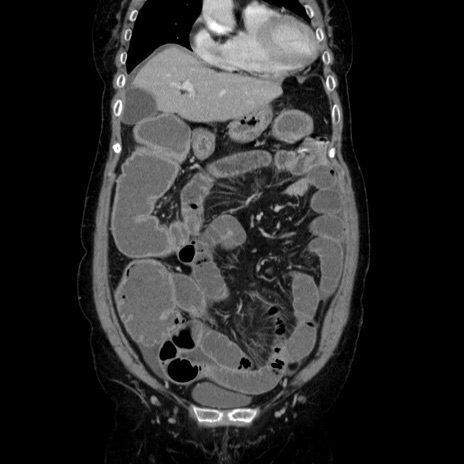

症例5(冠状断像)

【症例】70歳代女性

【主訴】お腹が張る

【現病歴】1週間くらい前から腹部膨満の自覚あり。昨日夜から増悪したため、本日救急外来受診。

【身体所見】意識清明、BT 36.5℃、BP 165/106mmHg、HR 80bpm、SpO2 98%、腹部:膨満、軟、自発痛・圧痛なし、触診にて不快感あり、腸蠕動音:減弱

【データ】WBC 12600、CRP 1.04